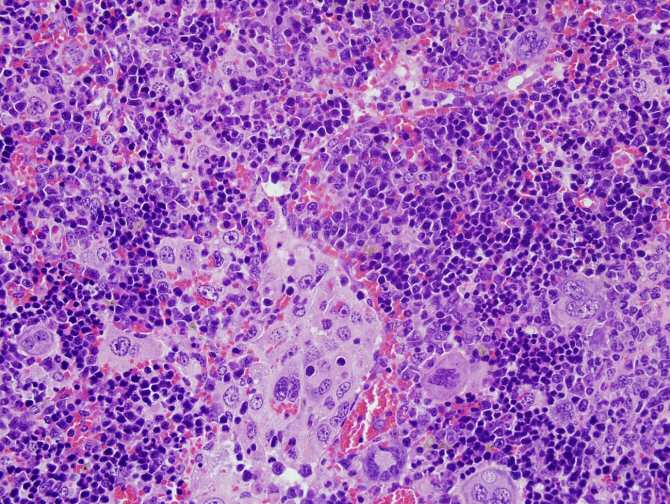

Imagen de microscopia de un linfoma desarrollado por ratones con alteraciones en el gen VAV1. (Foto: Xosé R. Bustelo)

El estudio también ha desarrollado un modelo animal que permite generar linfomas en ratones tras la expresión de mutantes de VAV1 en linfocitos T sanos. “Usando técnicas genómicas y bioinformáticas hemos podido comprobar que estos linfomas reproducen la gran mayoría de las características clínicas, patológicas y moleculares de los linfomas periféricos de células T en los pacientes”, añade el investigador del CSIC.